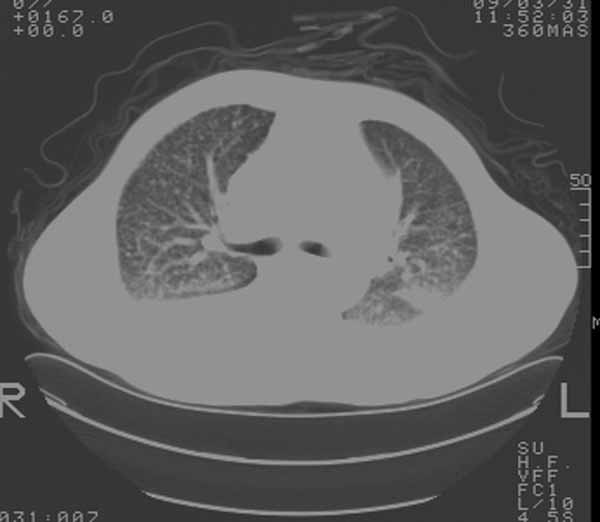

以下是引用余辉在2009-3-31 18:43:00的发言:[br]肺水肿,双侧心腔积液,心包积液,心影增大,疑似心衰

以下是引用wangyong1977在2009-3-31 20:46:00的发言:[br]肺水肿,双侧胸腔积液,心包积液,心影增大,疑似心衰 [br]

以下是引用宇宙ct在2009-3-31 18:57:00的发言:[br]肺水肿,双侧心腔积液,心包积液,心影增大,疑似心衰 [br] [br]